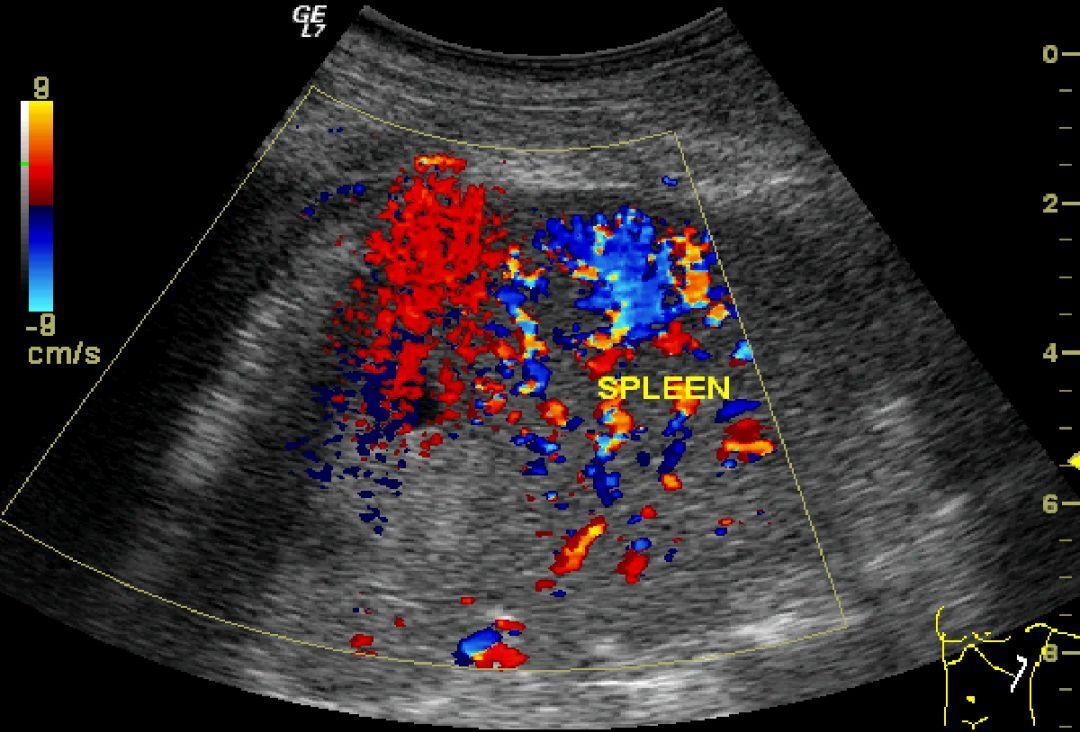

3、B超检查

腹部 b超检查在紧急情况下可以显示腹部器官的损伤,如腹腔积血等。